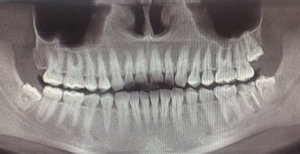

У меня под нижней семеркой киста, врач сказал, "и хорошая такая", сбоку образовался карман. Шестерка удалена в январе этого года, восьмерка не прорезалась. Зуб слегка подвижен, но он меня довольно редко беспокоит, это и была причина откладывания визитов к стоматологу. Не болит, изредка, при жевании дает о себе знать. Но хирург сказал - зуб на удаление, надо импланты ставить. Я читала, что есть способы лечить кисту и вполне успешно.

Есть ли смысл мне показаться другому врачу или зуб, все-таки не спасти?